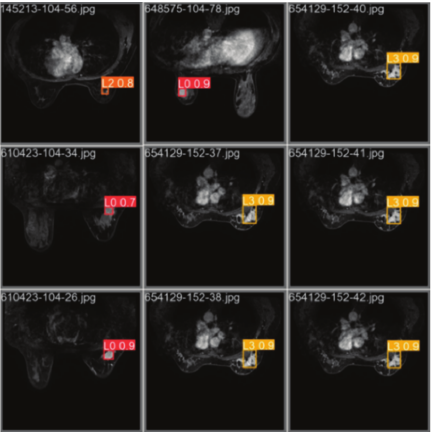

In the detection of breast cancer grading, human epidermal growth factor receptor 2 (HER-2) is a type of receptor that is strongly linked to the development and progression of breast cancer and serves as an important indicator of breast cancer prognosis and treatment 2. HER-2 classification testing is divided into four main categories: negative HER-2 (0), weakly positive HER-2 (\(1+\)), positive HER-2 (\(2+\)), and strongly positive HER-2 (\(3+\)). HER-2 breast cancer imaging for the assessment of classification mainly includes X-ray, ultrasound, and magnetic resonance imaging (MRI). Among them, MRI is one of the prominent non-invasive imaging techniques that breaks the traditional monomorphic diagnostic model by allowing for the quantitative and qualitative analysis of lesions. Fig. 1 shows an example of an MRI image of a breast cancer lesion. The position marked by the red ellipse in the first row is the lesion area. And MRI images in the second row show magnified detail of the lesions from the corresponding images in the first row. From which it can be observed that the small target is low-resolution and poorly characterized in the MRI image. The irregular shape of the lesion and the possible presence of multi-targeted lesions may result in failure to accurately identify them. In addition, there are many complicated scenes such as several confounding factors coexist, scars, architectural distortion, skin thickening, and implanting or foreign bodies that create artifacts and obscure posterior tissue. These complicated scenes make lesion detection and classification unusually difficult. Thus, MRI lesion detection in breast cancer remains a challenge, especially in small and multi-target lesions in complicated scenes.

Fig. 1. Examples of lesions labelled in red color.